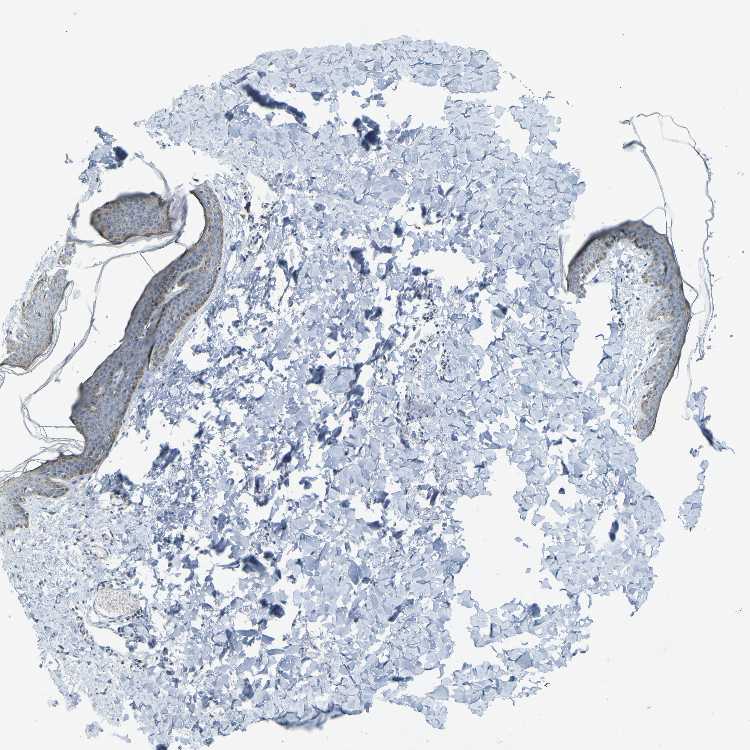

TISSUE PRIMARY DATA SKIN Show tissue menu

SKIN 1 - Antibody stainingi

Antibody staining in the annotated cell types in the current human tissue is reported as not detected, low, medium, or high, based on conventional immunohistochemistry profiling in selected tissues. This score is based on the combination of the staining intensity and fraction of stained cells.

Each image is clickable and will lead to virtual microscopy that enables deeper exploration of all samples and also displays staining intensity scores, fraction scores and subcellular localization as well as patient and tissue information for each sample.

Antibody HPA011861Antibody HPA012145

Langerhans MediumLow

Fibroblasts Not detectedLow

Keratinocytes MediumMedium

Melanocytes MediumMedium

SKIN 2 - Antibody stainingi

Epidermal cells LowMedium